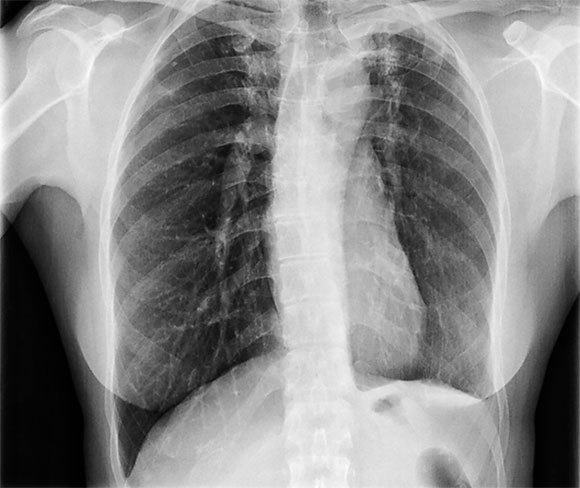

כ-1.5 מיליון איש מתו משחפת בשנת 2020. צילום חזה שמראה נזק לריאות כתוצאה משחפת | Dr. P. Marazzi, Science Photo Library